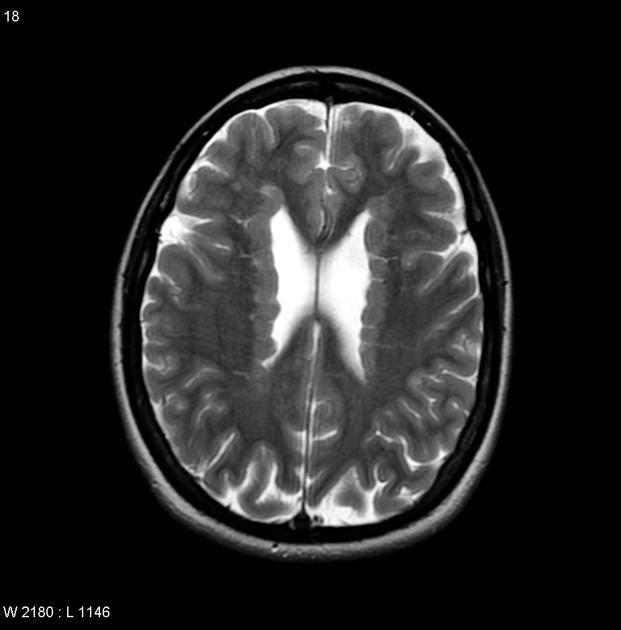

Diagnosis?

Imaging findings?

Dysgenesis of the corpus callosum- partial or complete absence of the corpus callosum.

High-riding 3rd ventricle, Bundles of Probst (tracks of white matter that run parallel to the ventricle as an alternative to the CC- thats why the lateral ventricles are farther apart), “bullhorn” appearance of the frontal horns, absent cingulate sulcus, absence of the septum pellucidum or severe widening of the cavum septum pellucidum, enlarged occipital horns (colpocephaly).

Associated with otehr CNS anomalies.